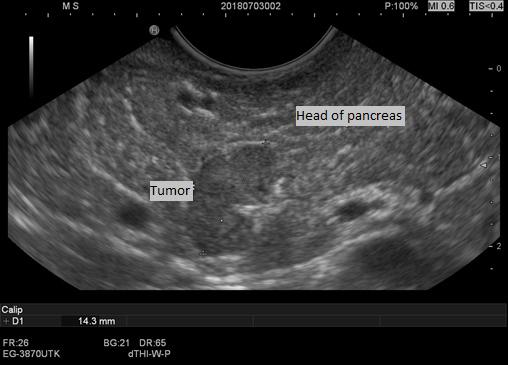

Postpartum hypoglycemia in non-diabetic women is a rare condition. We report the case of a 34-year-old woman who experienced neuroglycopenia 2 days after delivery. Corresponding to severe hypoglycemia, we found inappropriately elevated insulin and C-peptide levels. Following magnetic resonance imaging a lesion of 10×8 mm was detected in the head of the pancreas. An ultrasound-guided fine needle aspiration of the mass confirmed the diagnostic suspicion of a pancreatic neuroendocrine tumor. Complete surgical enucleation of the insulinoma resulted in immediate and permanent resolution of the hypoglycemia. The postoperative course was uneventful. Histopathological and immunohistochemical analyses were consistent with insulinoma. The diagnostic approach to postpartum hypoglycemia represents a challenge for multidisciplinary teamwork.

非糖尿病女性产后低血糖是一种罕见病症。我们报告一例34岁女性,她在分娩后2天出现神经低血糖症。与严重低血糖相对应,我们发现胰岛素和C肽水平异常升高。磁共振成像检查后,在胰头发现一个10×8毫米的病灶。对该肿块进行超声引导下细针穿刺活检,证实了对胰腺神经内分泌肿瘤的诊断怀疑。胰岛素瘤完整手术摘除后,低血糖立即得到永久性缓解。术后过程顺利。组织病理学和免疫组织化学分析结果与胰岛素瘤相符。产后低血糖的诊断方法对多学科团队合作而言是一项挑战。